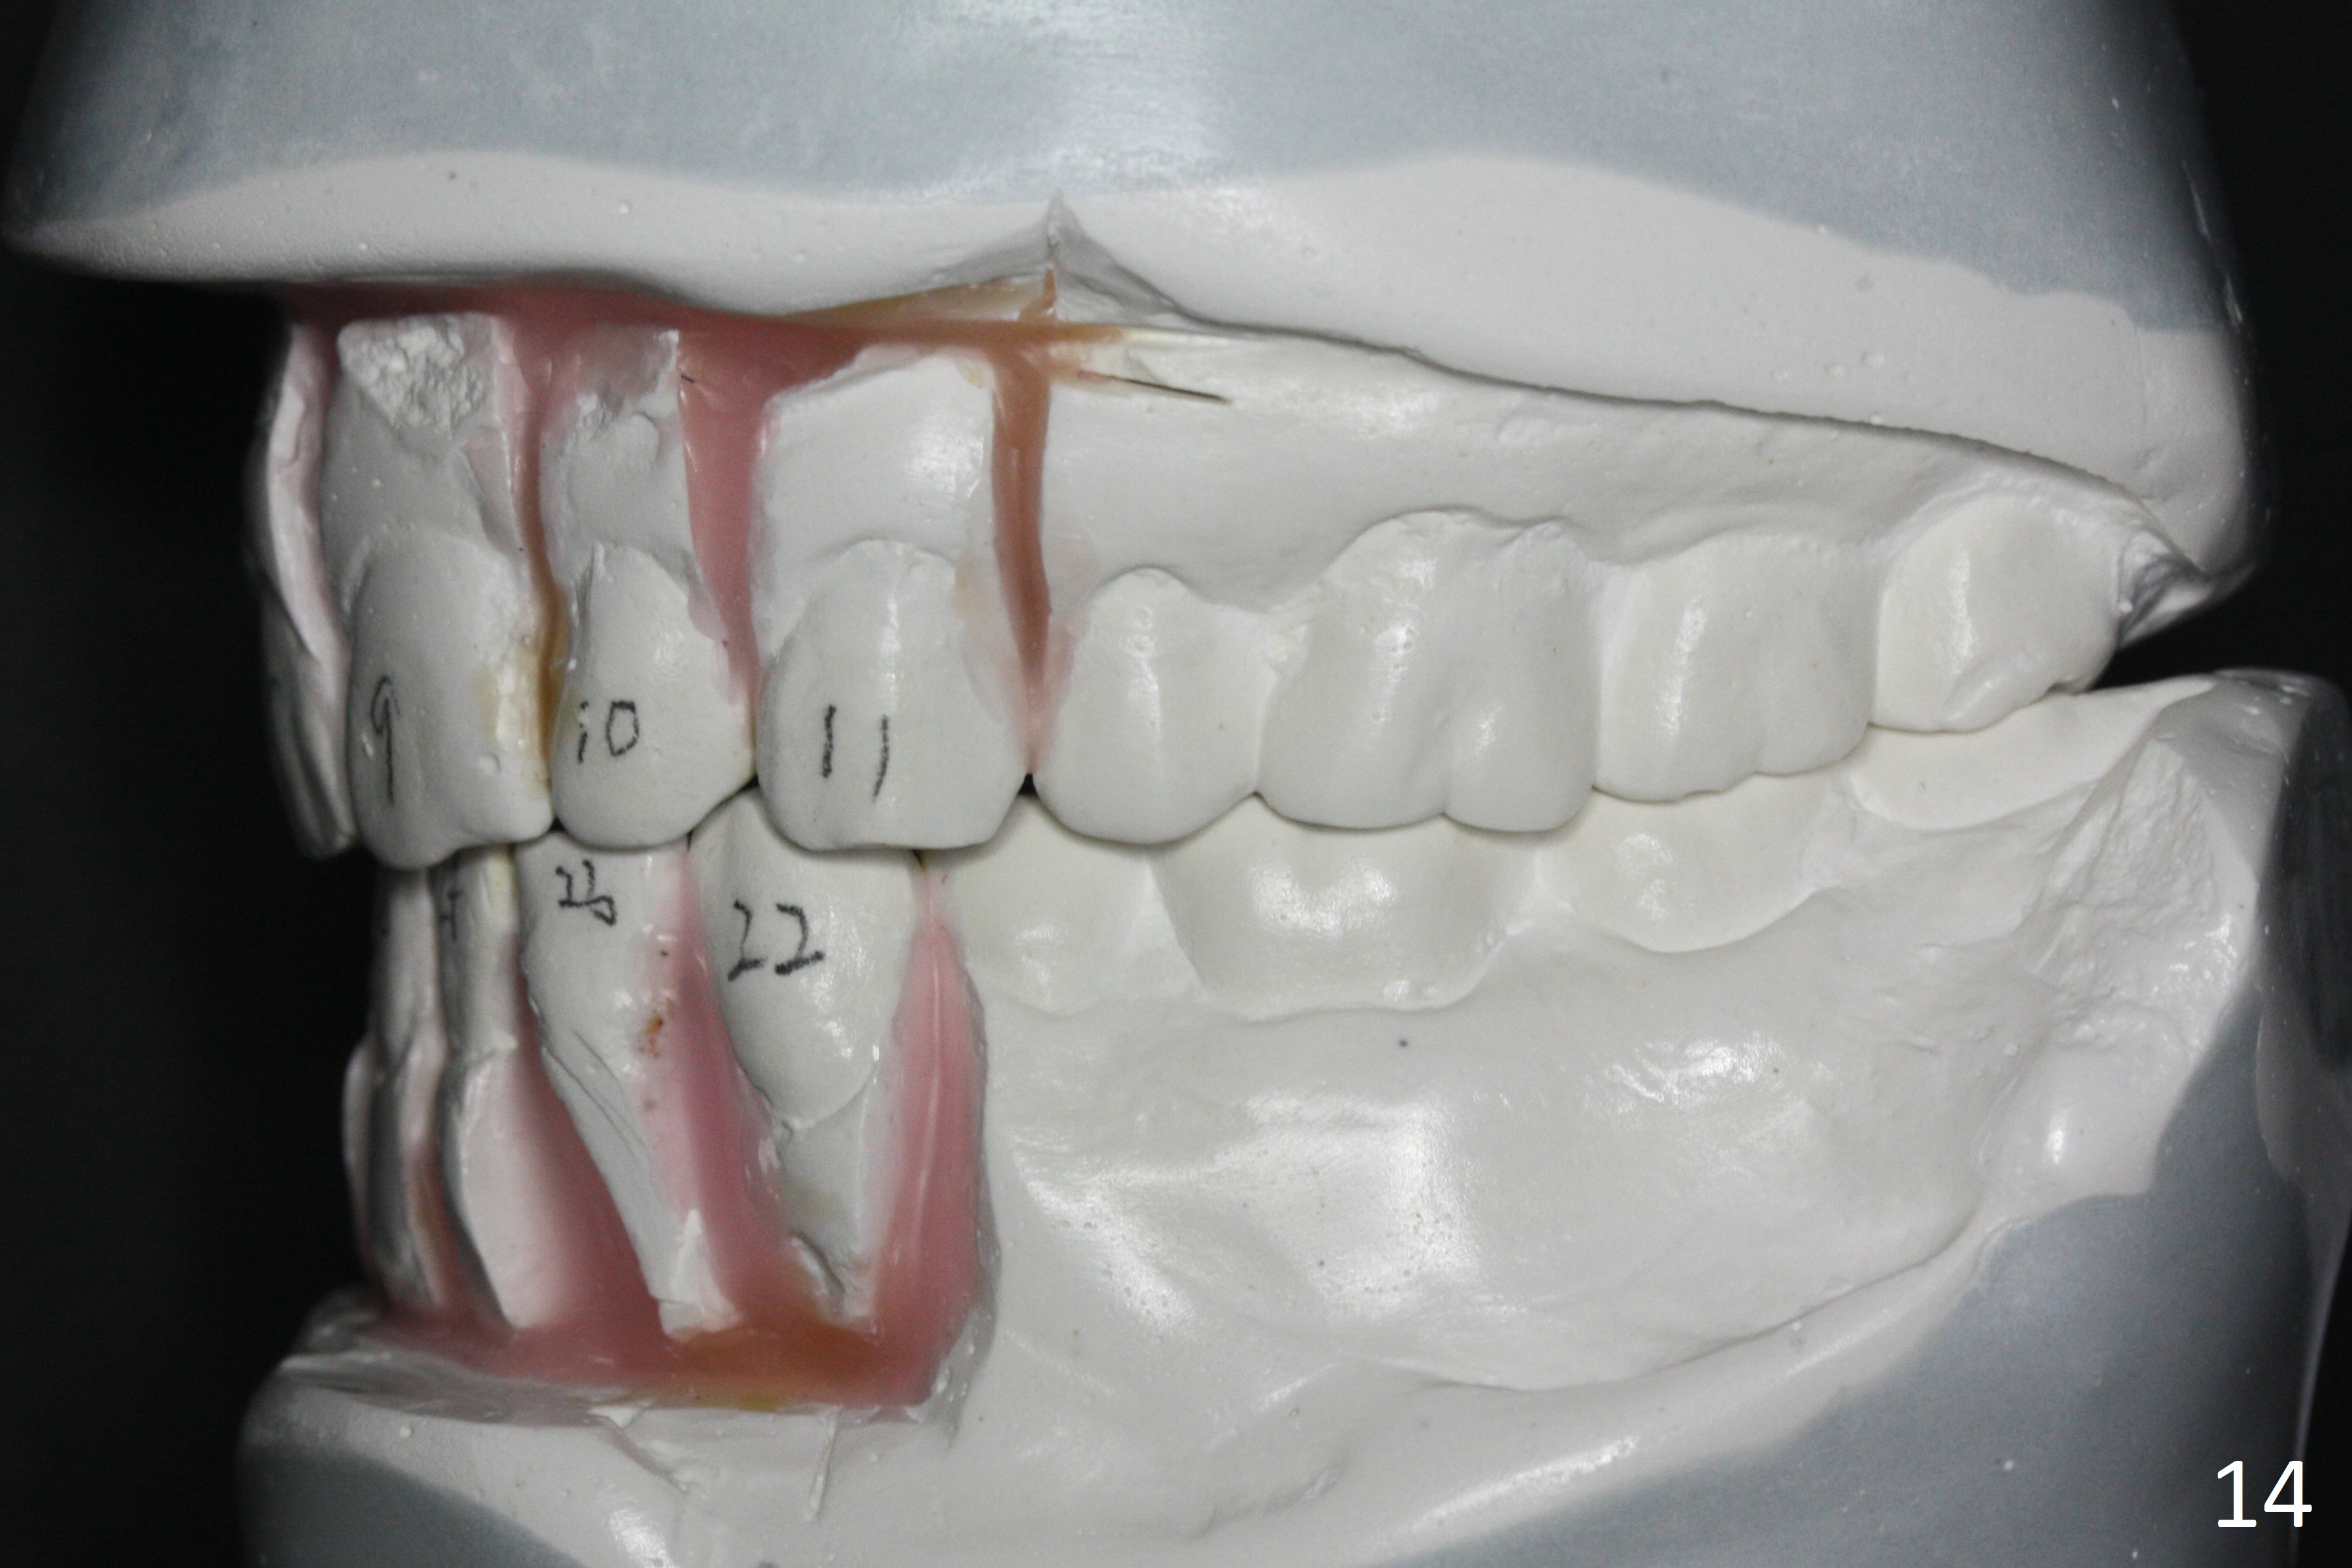

Enough Space For Crowding After Extraction? A 47-year-old man requests orthodontic treatment following SRP in other office (Fig.1-11). For severe crowding and midline shifting, extraction of four of the 1st bicuspids is imminent. Is it enough? To answer the question, model surgery is performed (Fig.12-16). 1st visit: periodontal maintenance, orthodontic consent (emphasizing oral hygiene) extract 4s and possibly L8s and separators. The beauty of this vist is that after local anesthesia and extraction including L8s, it is painless and easy to remove calculus from the proximal surfaces of the neighboring teeth. It is much easier to place separators after extraction. It is expected that there is no gingival erythema when the patient returns for bracketing. Take photos of UR3, similar to Fig.3. Molar banding is also anticipated to be easy with separator placement after extraction. Return to Ortho Cases Xin Wei, DDS, PhD, MS 1st edition 11/23/2017, last revision 04/28/2019